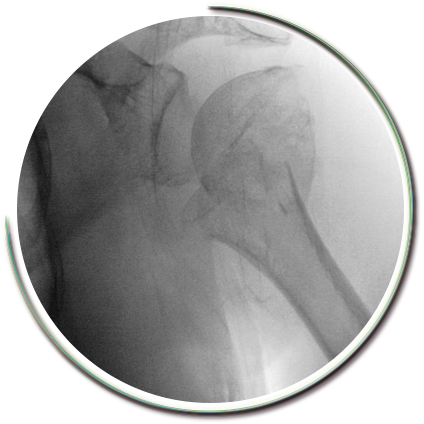

Proksimal humerus, kolun omuz eklemine yakın olan üst kısmının adıdır. Erişkin kırıklarının %5’ini oluşturur. Genellikle 60 yaş üzerinde, kemik mineral yoğunluğu düşük hastalarda basit düşmeler sonrasında oluşur. Genç hastalarda ise şiddetli travmalar ile oluşur.

Bu bölge kırıklarının %80’ini ayrışmamış kırıklar olup kol askısı ile tedavi edilebilirler. Parçalı kırıklar, kas gruplarının çekmesi nedeniyle ayrışıp, kayabilirler. İleri yaş ve yaşam kalitesindeki sınırlı beklenti nedeni ile kaymaların gözardı edilmesi, kaynamama ya da kötü pozisyonda kaynamaya yol açar. Bu durumda daha zor olan düzeltici cerrahiler ya da protez girişimleri gerekebilir.

Parçalı kırıklarda kaynama sorunları ve işlev kaybı oluşmaması amacıyla sınırlı girişimsel cerrahi müdahale gerekebilmektedir. Kırık parçaları için çok kıymetli olan kanlanma bozulmadan (travmanın kendisi kanlanmayı yeterince etkileyebilir) kırık tespiti güçlü bir şekilde yapılabilmektedir. Kırık düzeltilmesi, açılan kas pencerelerinden yapılır. Parçaların tamamına hakim olabilmek amacıyla dikişler ve kilitli vidalı plaklar kullanılır. Kullanılan pencereler yerleştirilen plaklara göre oldukça küçük boyutlardadır. Pencerelerin bölgeden geçen sinirlere uygun mesafede olması gerekir.